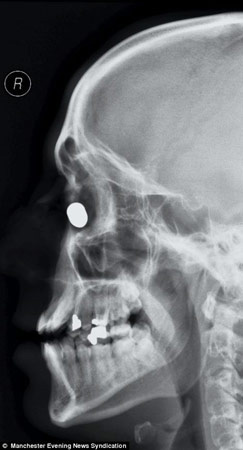

子弹卡在鼻骨处的X光片

当时,丹尼尔的朋友被这一幕惊呆了,枪声响过后,他们立即跑过去,抢下手枪。而抢劫犯也夺步逃走。丹尼尔很快被送往医院,医生惊异地发现,子弹虽然从丹尼尔面部穿过,但卡在了鼻骨处,并没有生命危险。

目前,医生已经将子弹从丹尼尔的鼻骨处成功取出,不过丹尼尔目前经常失眠、头疼,还需要一段时间才能恢复。